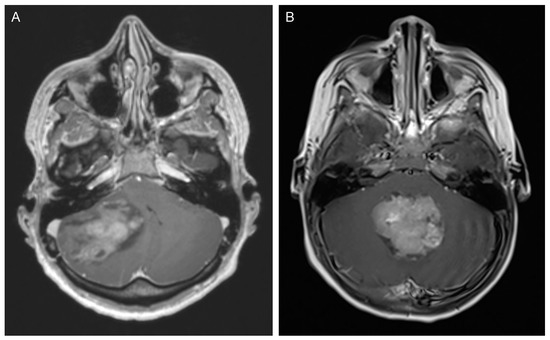

2. Medulloblastoma

2.1. Incidence and Classification

2.2. Clinical Presentation and Diagnostic Tools

2.3. Management and Outcome